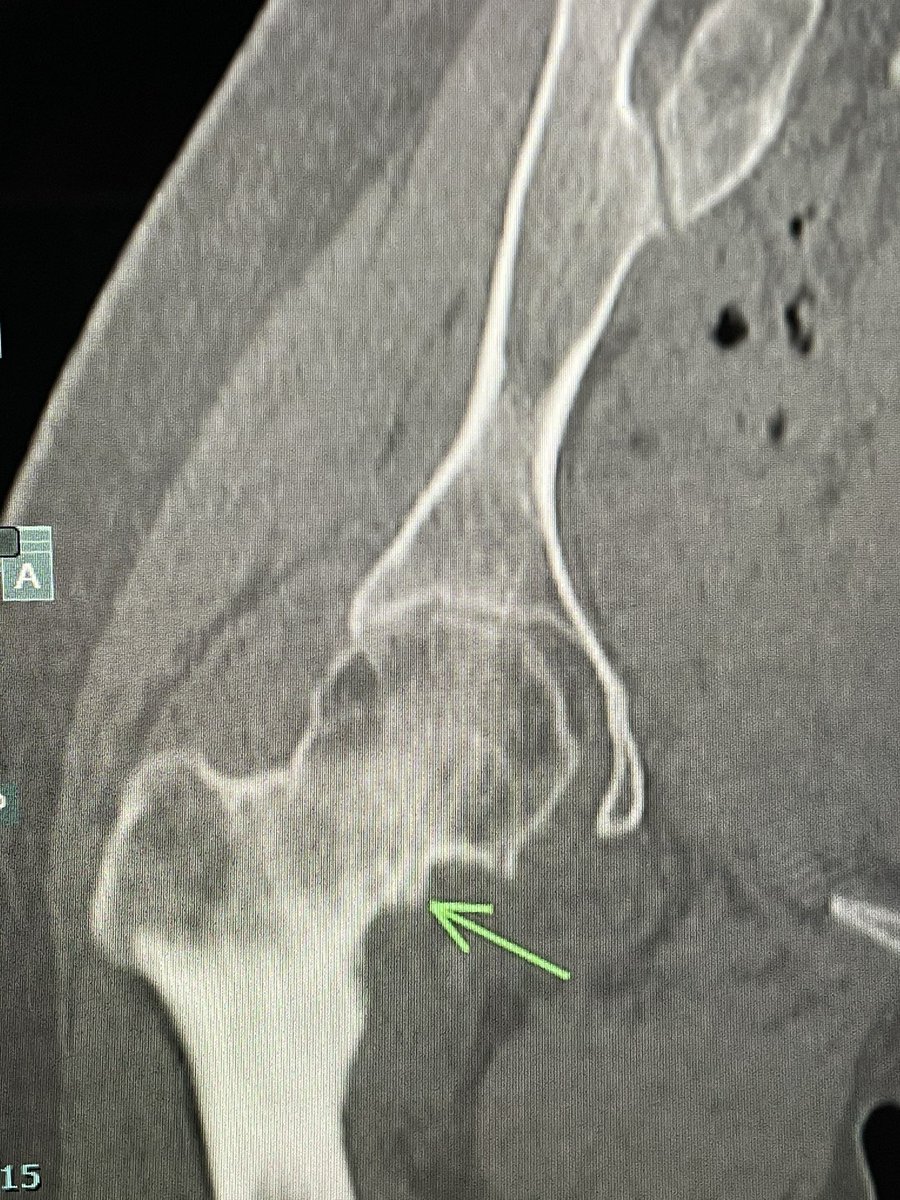

I had an opportunity to perform Intraarticular Osteoid osteoma RFA under GA

@alokmittaldr

CT confirmed it.

19 yr girl with chronic rt hip pain. One of my colleague @samrad77 diagnosed it intraarticular osteoid osteoma- rt femoral neck. I wasn’t sure.